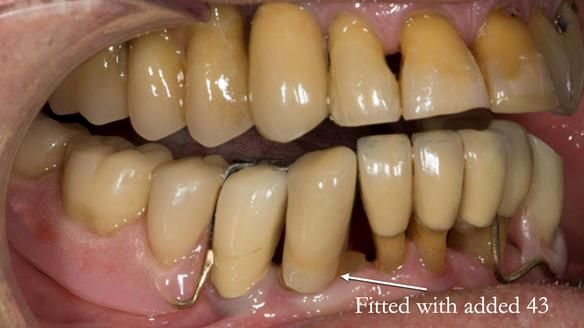

In 2022, tooth 43 fractured.

An artificial tooth was added to the RPD

by welding a cobalt–chrome tag to the bar

and adding the tooth.

The denture continued to function extremely well.